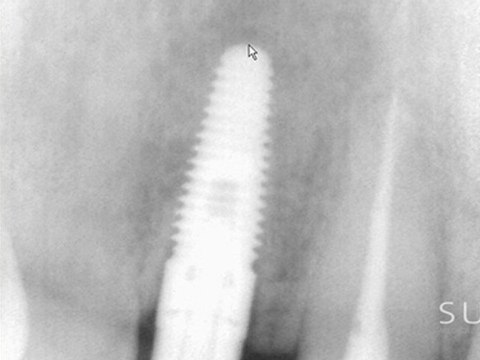

Intraoral, Case, Studies, Imaged, with, Suni, Sensors, Chapter